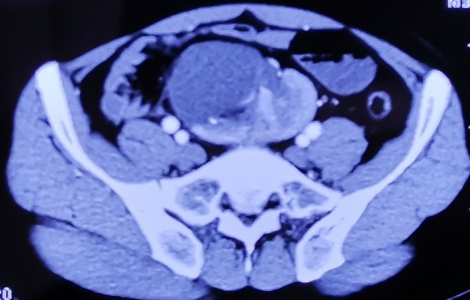

患者男,22岁,因“查体发现异位肾4年,左下腹疼痛1周”就诊,无尿频尿急尿痛,无肉眼血尿等其他临床症状,B超检查显示左侧异位肾,肾盂肾盏积水。行逆行造影检查显示左肾异位,左肾盂明显积水。行CTA(CT血管造影)检查显示左肾区空虚,盆腔内见异位肾体,异位肾门朝前。右侧髂总动脉及肠系膜下动脉发出分支分布于异位肾,异位肾静脉汇入下腔静脉下段,异位肾肾盂明显扩张。行ECT(利用放射性核素的检查方法)检查显示GFR:左肾8.88ml/min,右肾49.45ml/min,总值58.33ml/min。考虑患者左肾功能受损伴下腹部疼痛,遂行达芬奇机器人辅助腹腔镜左侧异位肾肾盂成形术。

术后6周复查患者疼痛消失,查血显示尿素氮 4.30 mmol/L,肌酐 92 μmol/L,肾小球滤过率 101.350 ml/min,CT显示肾盂积水明显减轻。